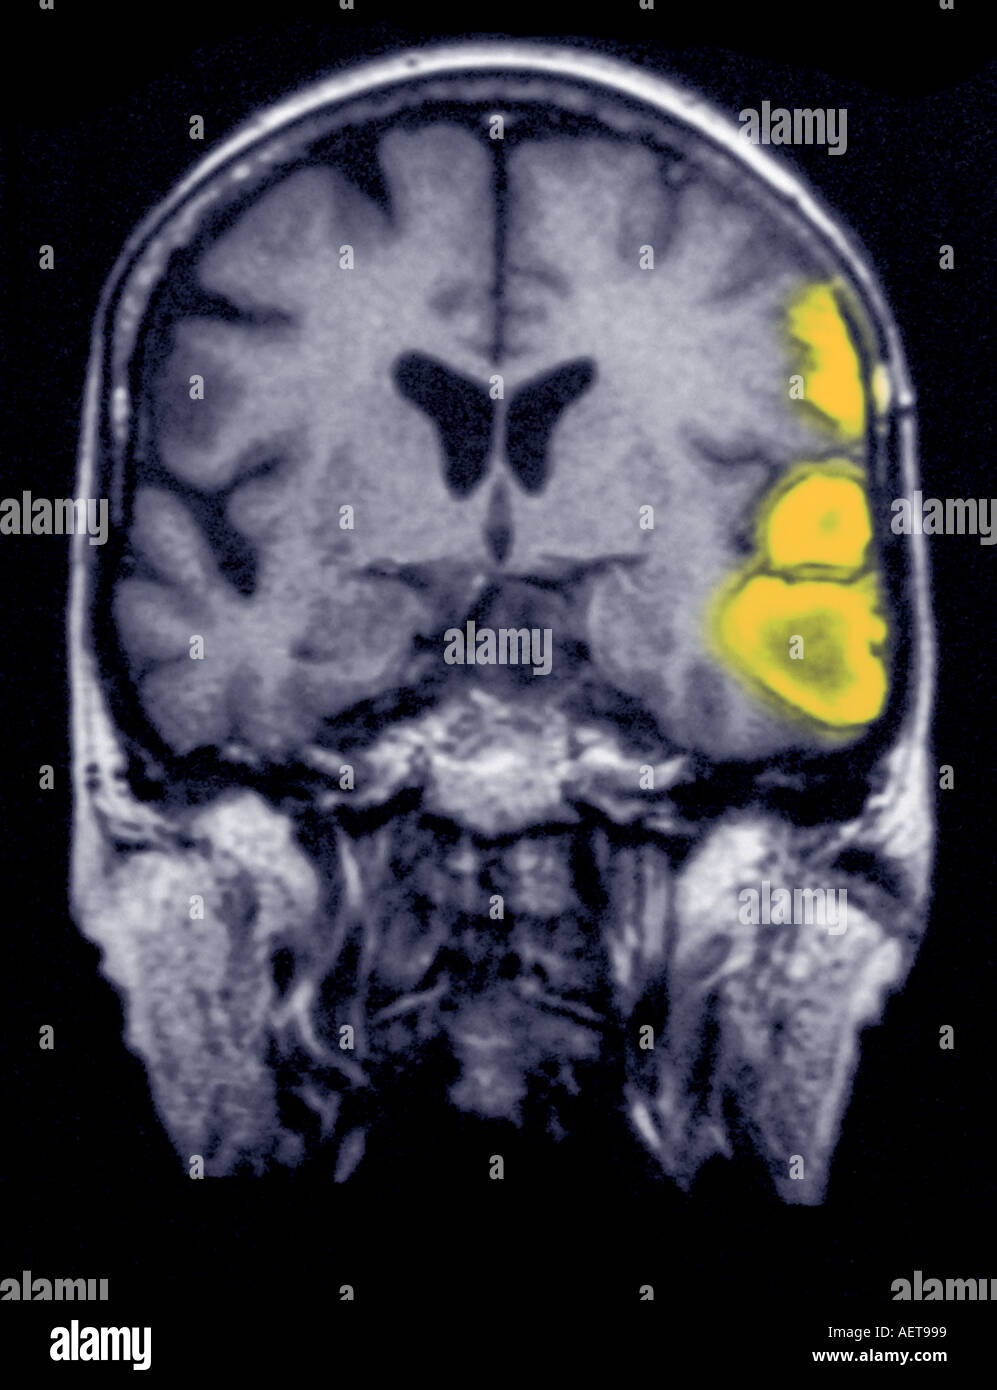

Temporoparietal Brain Hemorrhage In A 77 Year Old Female ... Magnetic resonance imaging. Large intracranial hemorrhage ... acute ICH Brain Hemorrhage Mri